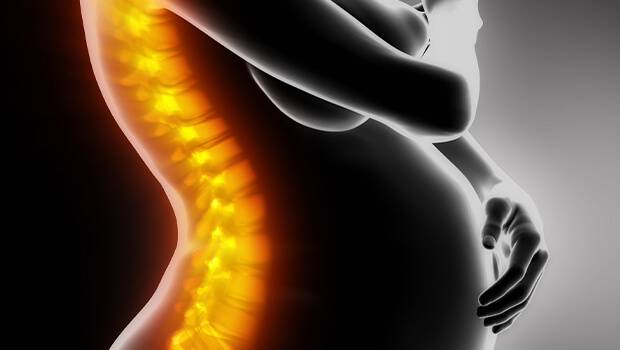

تنگی کانال نخاعی

احساس درد در ستون فقرات میتواند دلایل مختلفی داشته باشد. تنگی کانال مطالعه

آیا زایمان طبیعی بیدرد عوارضی دارد

پیشنهاد و توصیه اغلب پزشکان این است که اگر شرایط مادر برای مطالعه